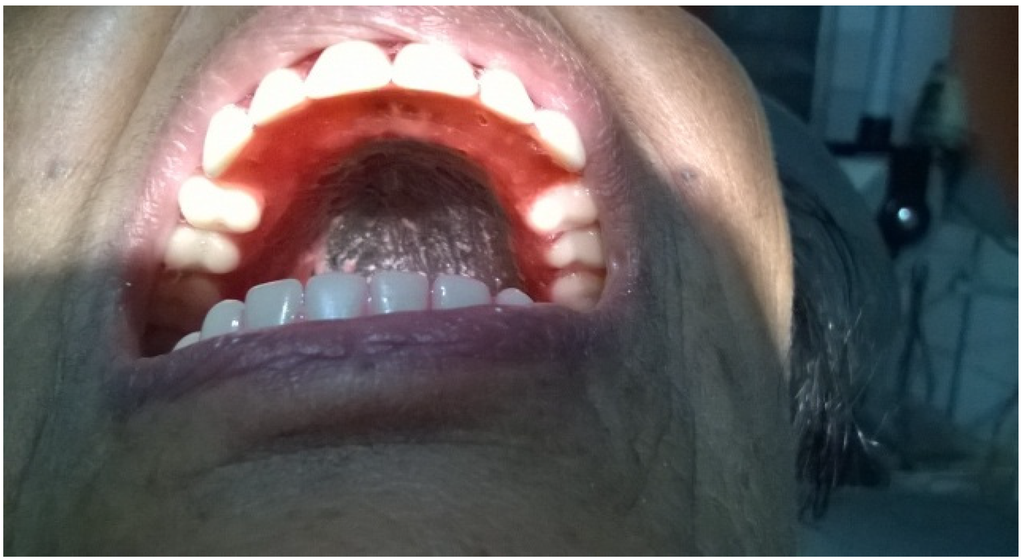

2. Case Presentation

3. Discussion